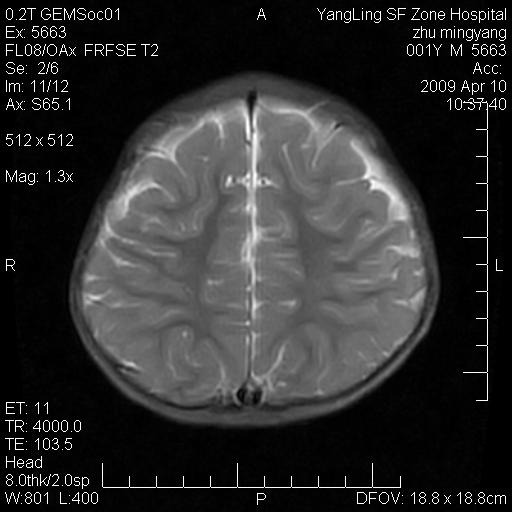

患者:1岁半,两天前外伤收住我院,ct检查小脑占位

考虑星形细胞瘤,建议增强

髓母细胞瘤或血管母细胞瘤,增强后可以鉴别;影像资料见 <。鱼博浪老师的《中枢神经系统ct与mr鉴别诊断》 小脑部肿瘤章节。

髓母细胞瘤或血管母细胞瘤!支持!

支持考虑髓母细胞瘤

考虑----髓母细胞瘤可能性大

考虑髓母细胞瘤或室管膜瘤。

支持髓母细胞瘤。

考虑髓母细胞瘤。

考虑髓母细胞瘤或星形细胞瘤

考虑髓母细胞瘤.

考虑髓母细胞瘤可能性大。

小脑肿瘤.考虑髓母细胞瘤可能.

就病灶部位及临床资料首先考虑髓母.